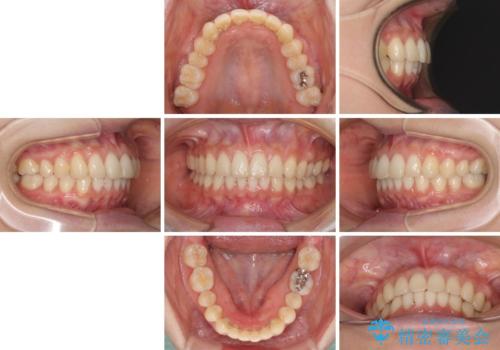

インビザラインによるディープバイトの改善

- 口元の前突感と深い咬み合わせ(ディープバイト)を気にして来院された患者様です。

インビザラインによる上下歯列の遠心移動(後方移動)と、それに伴う近心傾斜(前方傾斜)の改善により、口元の突出感とディープバイトを改善することとしました。

前歯のデコボコを最も気にしていましたが、咬み合わせが深く歯ぎしりが自由にできない点を指摘すると、常に食いしばってしまうことも悩みであることが分かりました。

咬合状態が大きく変化したため、治療後半では咬み合わせの位置が定まらなくなりました。上下の前歯に後戻り防止用のワイヤーを装着し、奥歯の咬合をフリーにしたことで1ヶ月ほどで咬み合わせが定まりました。